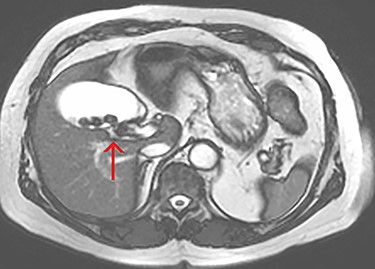

Axial view of the liver and gallbladder from a cardiac MRI showing the normal location of the cystic duct entering Hartmann’s pouch (highlighted by the arrow), which is separate and distinct from the structure shown in figure 1.

The tubular structure was remote from the porta hepatis with one lumen. It was located within the distal gallbladder fossa. Inspection of the gallbladder demonstrated an opening at the same orientation and of the same calibre as this tubular structure, raising suspicion for a duplicated cystic duct. Probing the source of the bile leak confirmed a single lumen. The capacity to perform IOC was not available at the time of the operation. A review of the patient’s prior imaging was performed. Recent cardiac magnetic resonance imaging (MRI), while not dedicated magnetic resonance cholangiopancreatography (MRCP), provided adequate views of the liver, gallbladder and biliary tree to demonstrate the suspected anomaly. On these images, two structures were seen to be connecting the gallbladder to the biliary tree. One duct was observed at Hartmann’s pouch, while a second connected to the gallbladder body (Fig. 1, Fig. 2). The images confirmed suspicion of a duplicated cystic duct and the decision was made to clip the lumen. The cholecystectomy was completed and a drain placed in the gallbladder fossa.